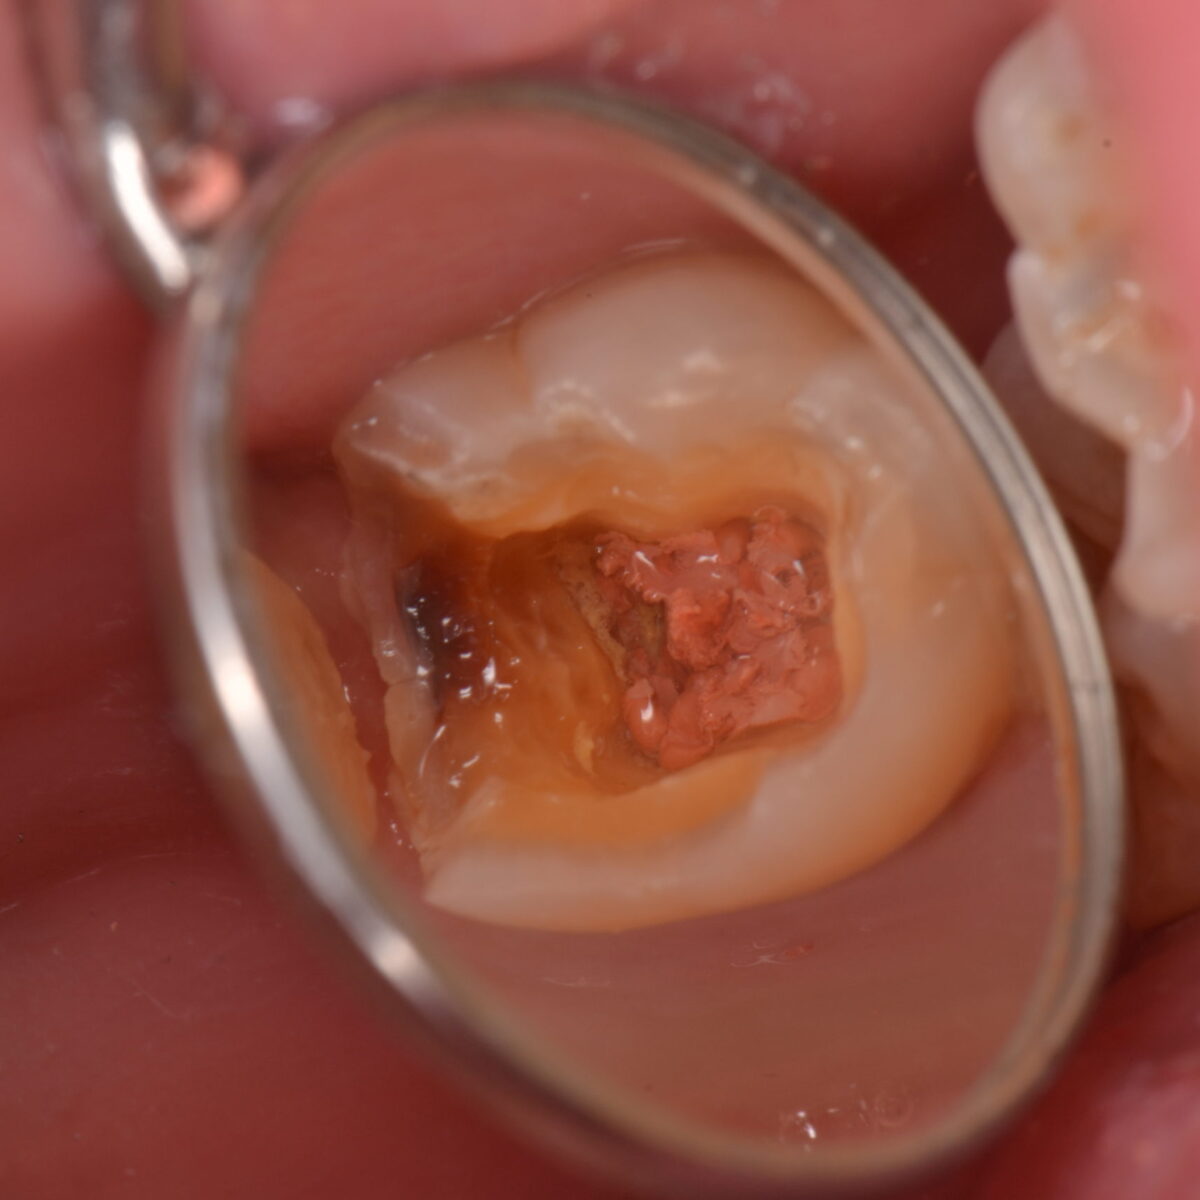

どこにあるのかわかりますか?12

【東京メトロ東西線妙典駅 徒歩5分の歯医者】市川、妙典の歯科医院、めぐりデンタルクリニックの梶原です。 前回の記事はこちらです(/・ω・)/↓ どこになるのかわかりますか?11 &…